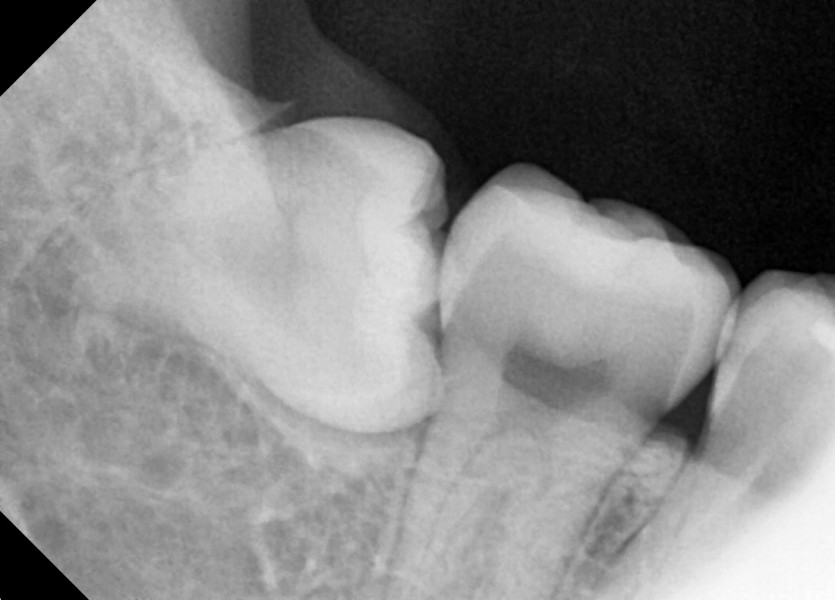

#38,48 사랑니 발치

구강 외과 전문의가 당일 발치했습니다.